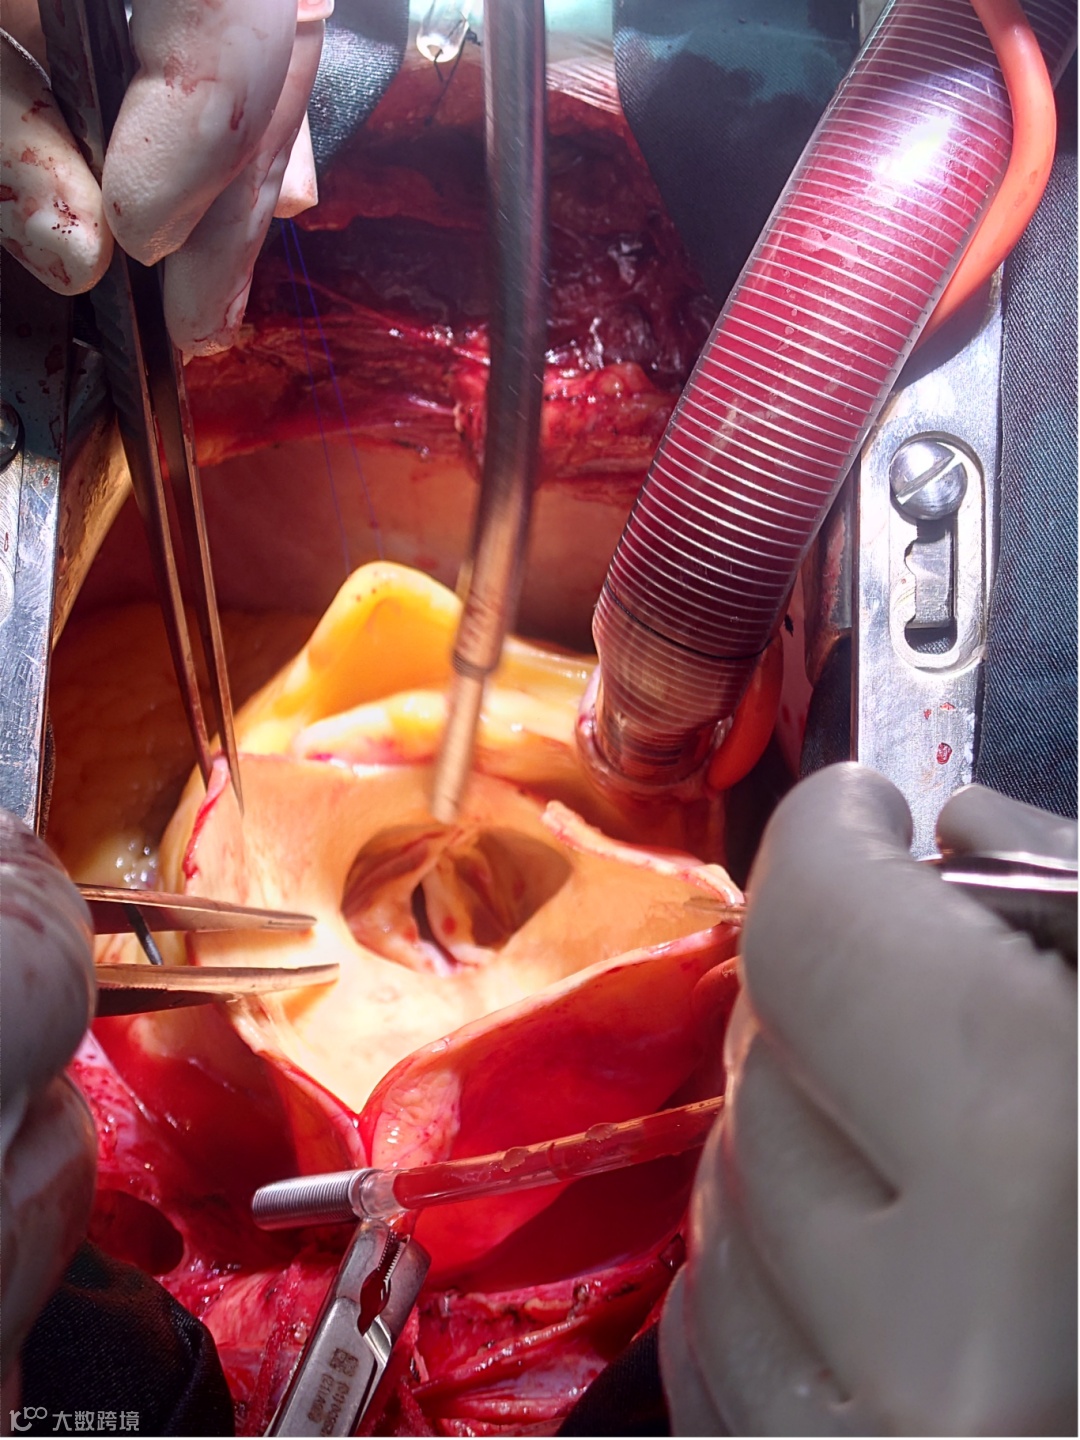

1、利用食道超声、脑氧检测技术与多个临床科室密切协作,开展疑难心脏手术、肝脏手术的术中监测和评估,大大降低了围术期并发症和死亡率的发生。